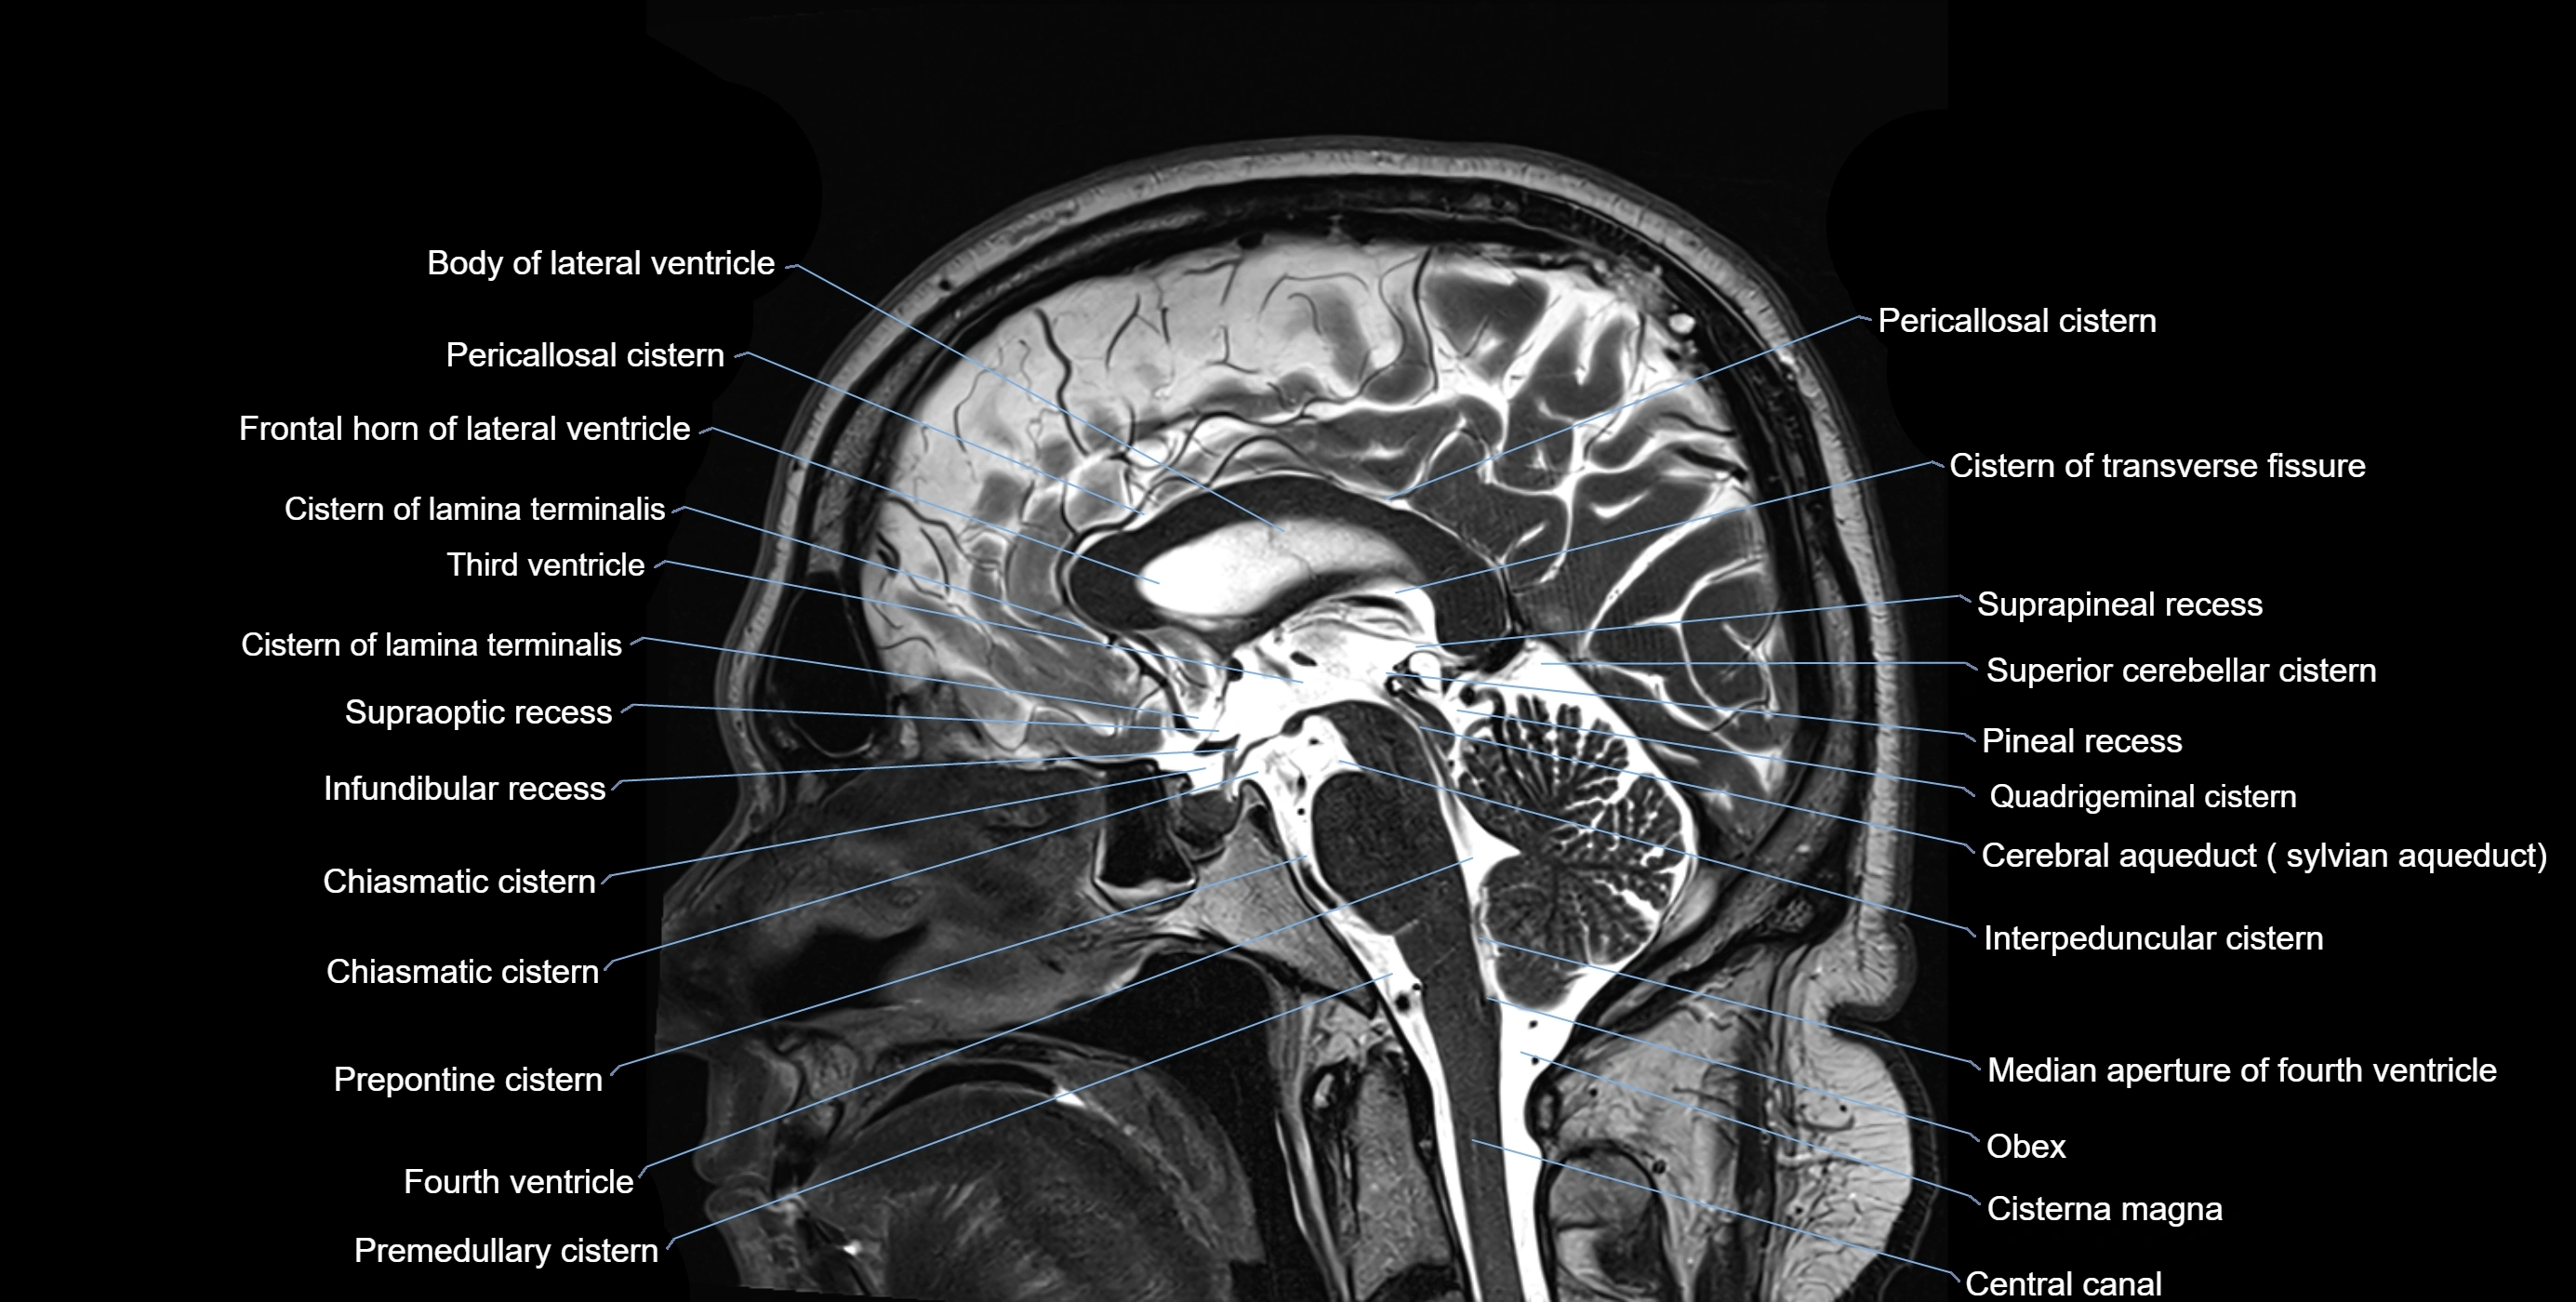

The ambient cistern is a paired, narrow, and elongated subarachnoid space located bilaterally along the lateral aspect of the midbrain. It serves as a conduit between the interpeduncular cistern anteriorly and the quadrigeminal cistern posteriorly. This cistern houses critical neurovascular structures, including parts of the posterior cerebral artery, superior cerebellar artery, trochlear nerve (cranial nerve IV), and the basal vein of Rosenthal. It plays an important role in the circulation of cerebrospinal fluid (CSF) and provides an anatomical corridor for various vessels and nerves passing around the midbrain.

MRI Appearance

• T1-weighted images:

• The ambient cistern appears as a region of low signal intensity, matching the dark appearance of CSF.

• Neurovascular structures within the cistern may appear as flow voids (signal loss from flowing blood) or as small dark linear structures.

• T2-weighted images:

• The cistern is hyperintense (bright) due to the high water content of CSF.

• Encapsulated vessels and nerves are seen as flow voids or hypointense lines within the bright background.